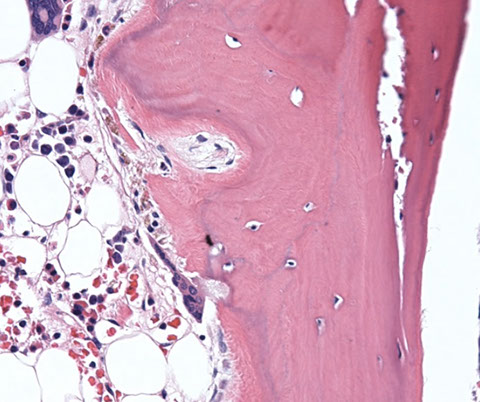

sites of hematopoiesis [1]

Normal trabecular bone

Type 1 collagen fibrosis